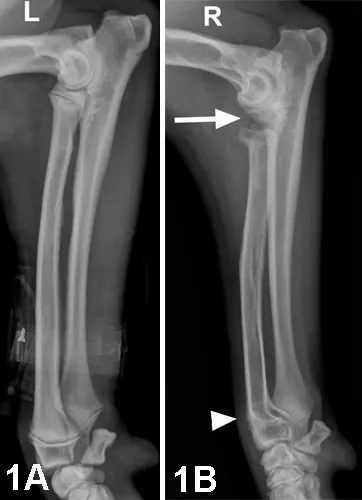

Outcome: A right radial lengthening was performed, incorporating a cortical graft obtained via ulnar ostectomy. Patient lameness and elbow pain completely resolved within 3 months postoperatively.

Figure 2. Immediate postoperative lateral view (2A) with prematurely closed right radial physis of the right radius and ulna (arrowhead) and humero-ulnar incongruity (arrow). Lateral view (2B) shows the right radius and ulna 2 years after surgery, demonstrating greatly reduced incongruity and complete healing of the radius and ulna.